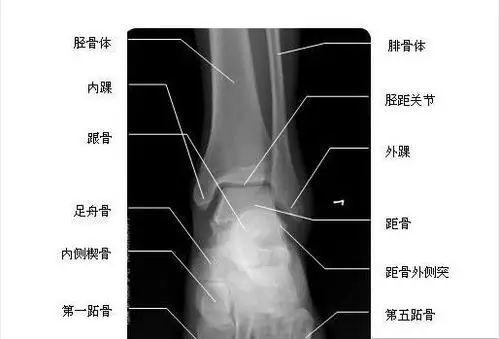

我们平时所说的踝关节,只是足的其中一个关节,指的是腓骨,胫骨,距骨

脚踝也可以叫踝关节,是脚与腿相连的部位,包括7块跗骨加上足部的跖骨

在解剖学上,脚踝(拼音:jiǎo huái),或称踝关节是人类足部与腿相连的